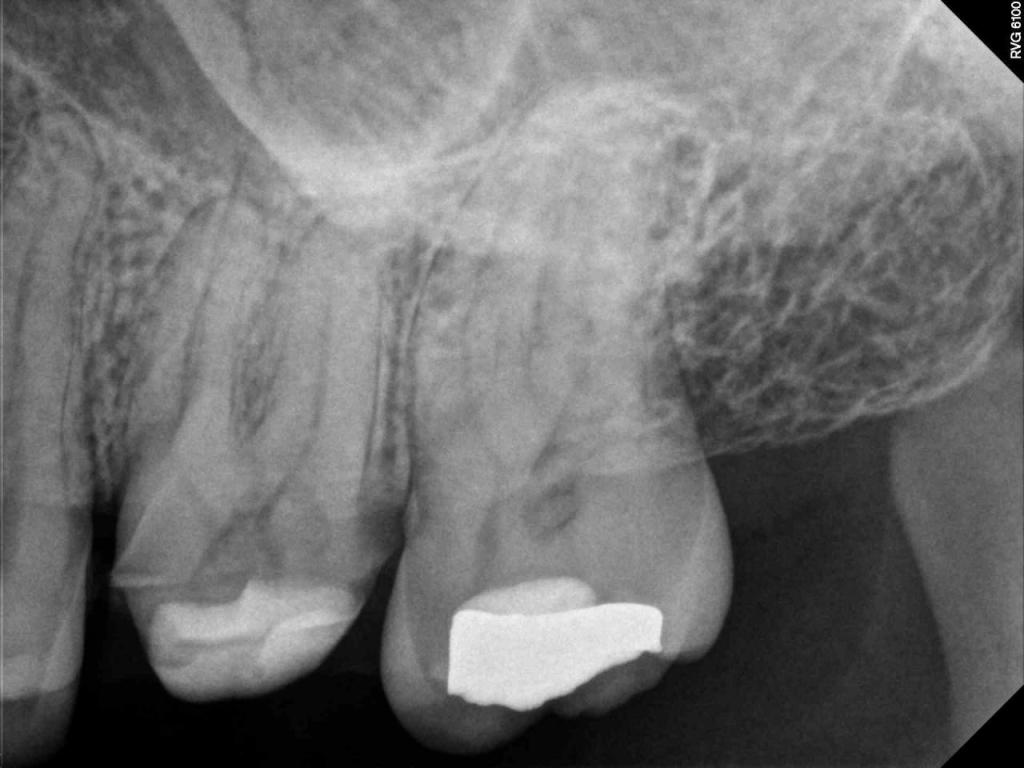

Although the primary use of visual documentation is for patient charts, dental images provide a meaningful way to communicate with patients about their care needs. Digital imagery is a vital tool for educating patients and an essential way to share information with office staff, colleagues and referring doctors. Digital technology has allowed Southcenter Endodontics to enhance our practice and improve the delivery of care to our patients. Below you will see images of “Before” and “After” scenarios. By clicking on a thumbnail image below, you will be able to see and a larger view of the x-ray taken at Southcenter Endodontics and notations made regarding each film.